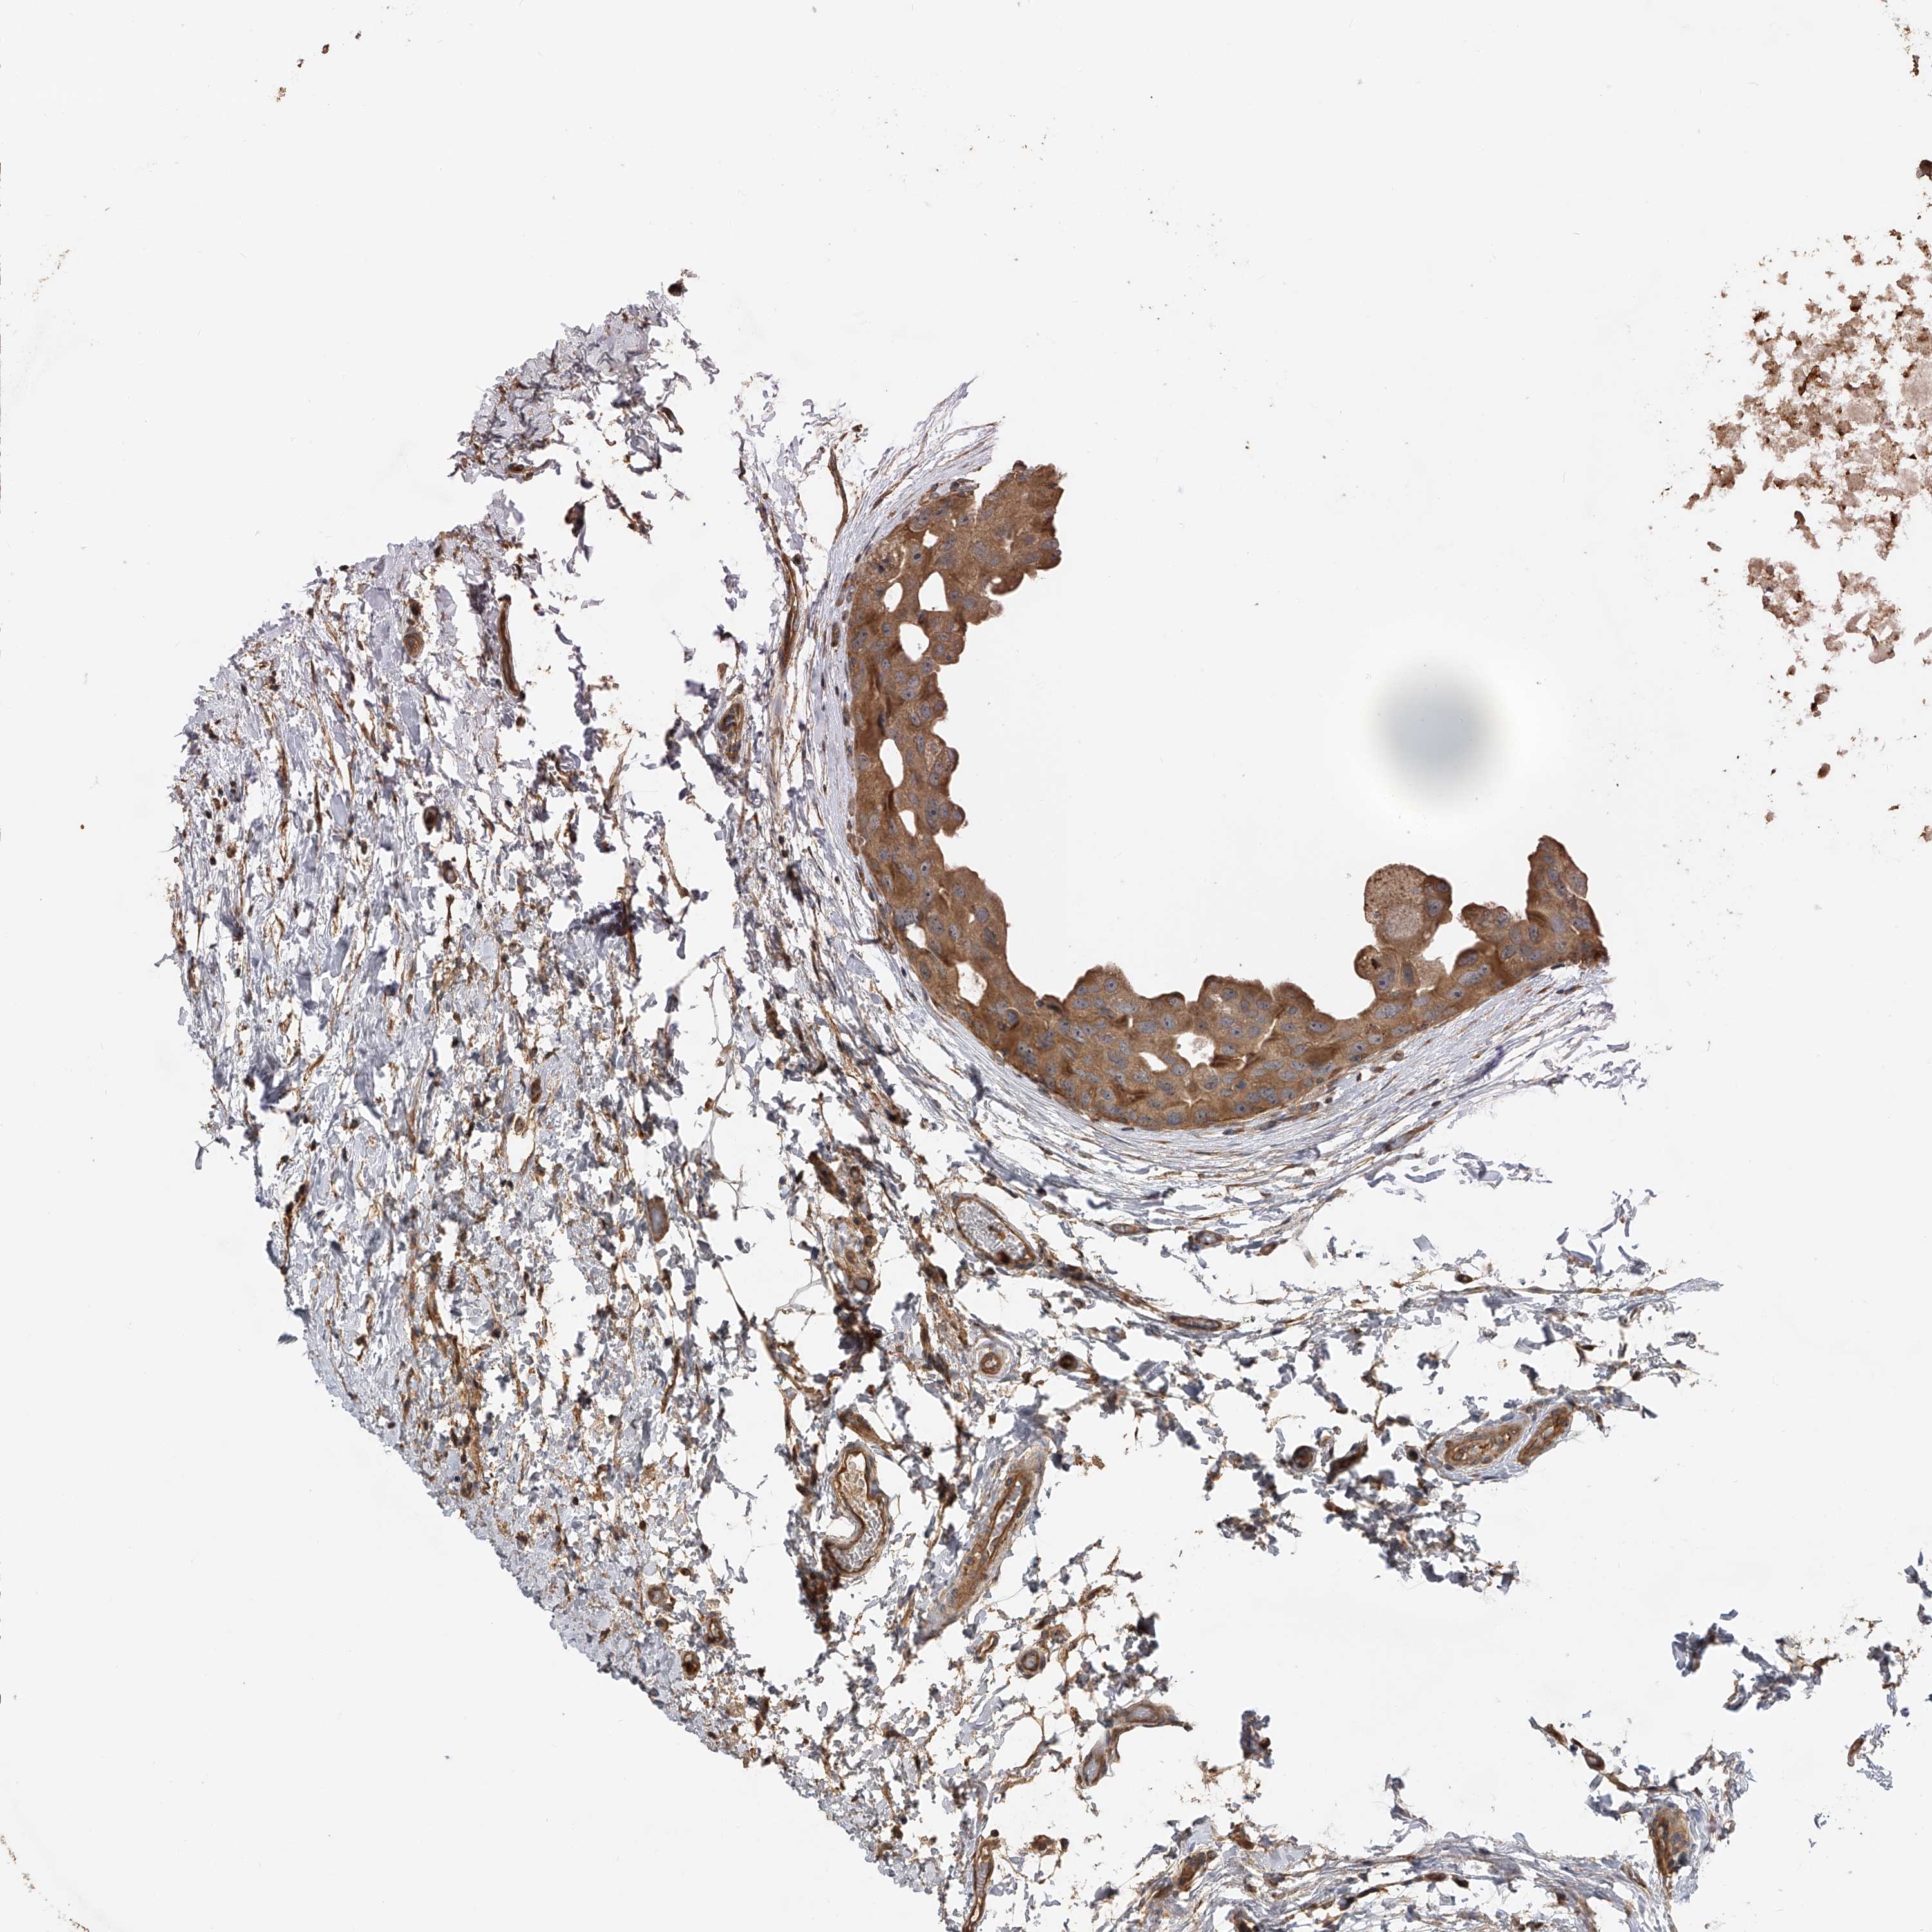

CANCER BREAST CANCER Show tissue menu

BRCA TCGA BRCA VALIDATION PROTEIN EXPRESSION

Breast cancer

Human cancer